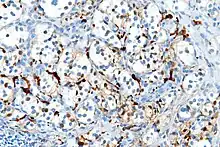

| Micrograph of a carotid body tumor (a type of paraganglioma). | |

On microscopic inspection, the tumor cells are readily recognized. Individual tumor cells are polygonal to oval and are arranged in distinctive cell balls, called Zellballen.[8] These cell balls are separated by fibrovascular stroma and surrounded by sustentacular cells.

With immunohistochemistry, the chief cells located in the cell balls are positive for chromogranin, synaptophysin, neuron specific enolase, serotonin, neurofilament and Neural cell adhesion molecule; they are S-100 protein negative. The sustentacular cells are S-100 positive and focally positive for glial fibrillary acidic protein. By histochemistry, the paraganglioma cells are argyrophilic, periodic acid Schiff negative, mucicarmine negative, and argentaffin negative.

Micrograph of a carotid body tumor

S100 immunostain highlighting the sustentacular cells in a paraganglioma